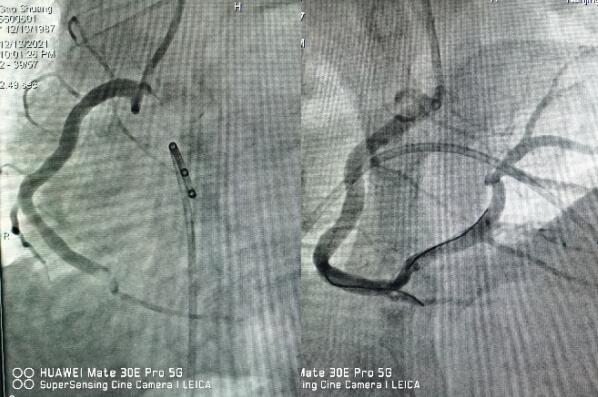

醫(yī)生立即予以搶救,并第一時間通知心內(nèi)科值班醫(yī)師,緊急啟動綠色通道,全院相關(guān)科室全力配合,心內(nèi)科介入團隊分工明確,迅速啟動導(dǎo)管室。因患者心梗后并發(fā)嚴(yán)重心律失常,為了安全起見,造影前植入臨時起搏器,造影提示右冠狀動脈急性完全閉塞,并成功開通血管,患者胸痛即刻緩解,目前正在康復(fù)過程中。